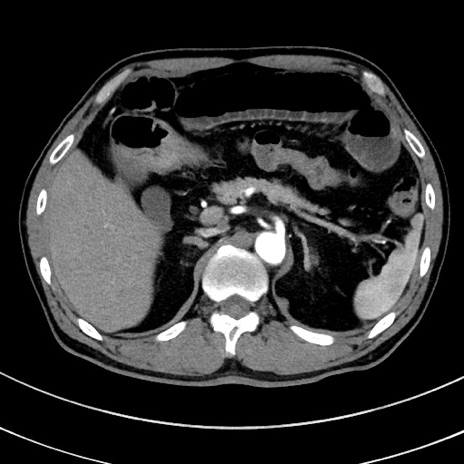

症例8(横断像)

【症例】 60歳代男性

【主訴】 黒色吐物

【現病歴】 4日前から嘔気自覚、2日前の朝食後にも嘔気あり、自分で手で嘔吐反射起こし嘔吐したところ血が混ざっていたため受診。

【既往歴】 5年前汎発性腹膜炎を伴う急性虫垂炎で手術、高血圧、前立腺肥大症、高脂血症

【身体所見】 腹部正中に手術癩痕あり 腹部平坦・軟圧痛なし膨満感あり

【データ】WBC 8400、CRP 4.54